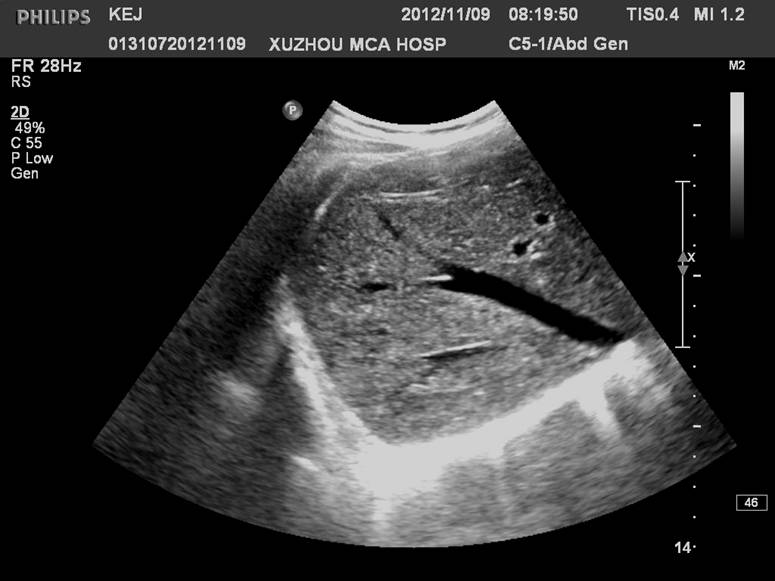

门静脉右支较短,约1.5cm左右,向右水平走行分成右前支和右后支,前支和后支分别再分成上段支和下段支:

门静脉右干及分支,当探头沿着门静脉主干右上方移动可显示右干,其远端“Y”型分叉:

门静脉主干及右支长轴和胆囊长轴呈空间"垂直",立体投影空间排列呈"飞鸟样":